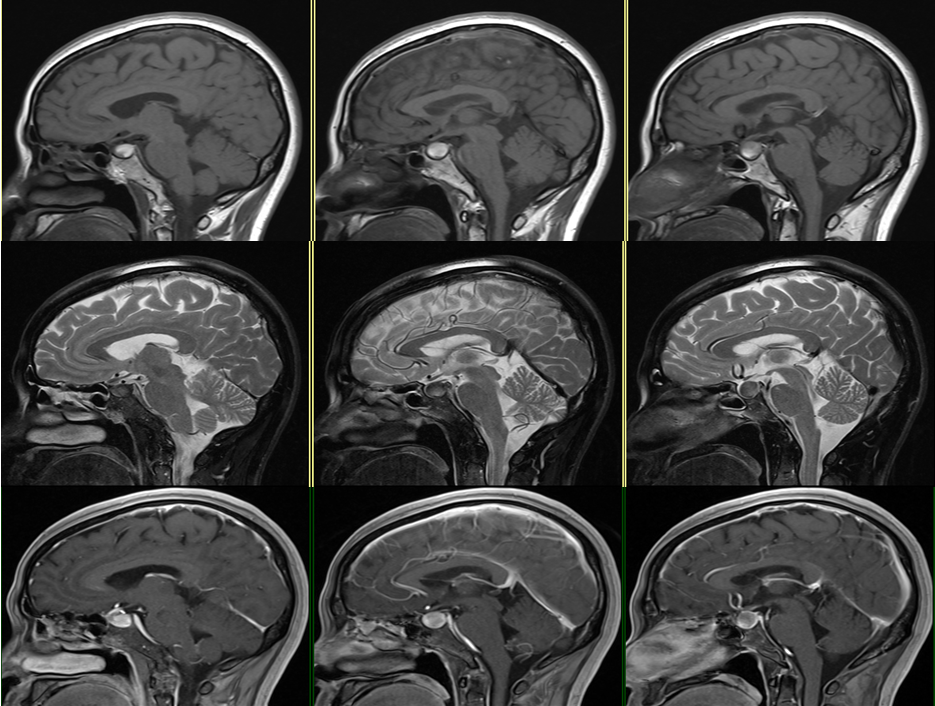

case 15:一年半前偶然发现,无明显症状,怀疑垂体瘤卒中,服用过一段时间溴隐亭,后经北京天坛医院诊断 Rathke 囊肿后后停药,现复查较前片无变化。

看完 14 个病例,一起来认识这个表现多样的 Rathke’s囊肿

形态信号异常,与垂体瘤卒中难以鉴别,但与患者既往检查片比较无异常改变,遂考虑囊肿可能

T1WI 高信号症状性 RCC 与出血性垂体瘤卒中鉴别:

• 冠状面对称、体积较小、信号均匀、增强边界光滑清晰、囊内结节提示→RCC。

• 体积大,冠状面不对称、信号不均匀、增强边界毛糙、鞍旁结构受侵、分隔征、液液平面征则提示→垂体瘤卒中。

case 16:男,38y ,偶然发现

延迟强化,垂体微腺瘤

case 17:f/59y

强化高峰出现较正常垂体腺晚,在团注造影剂后 3 min 内为最佳时间。强化持续时间长,必要时延迟扫描,延迟期肿瘤较垂体腺显著强化,信号高于正常垂体腺。动态强化很有必要。